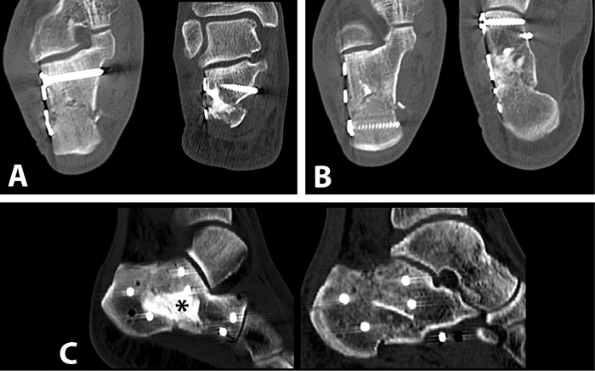

![]() |

Figure 35.35. Final x-rays. A. Lateral view. B. Broden’s view. C. Axial view.

Figure 35.36. Postoperative CT scans. A. Coronal cuts. B. Transverse cuts. C. Sagittal reconstructions showing body reposition. Calcium phosphate cement was used as void filler (*).